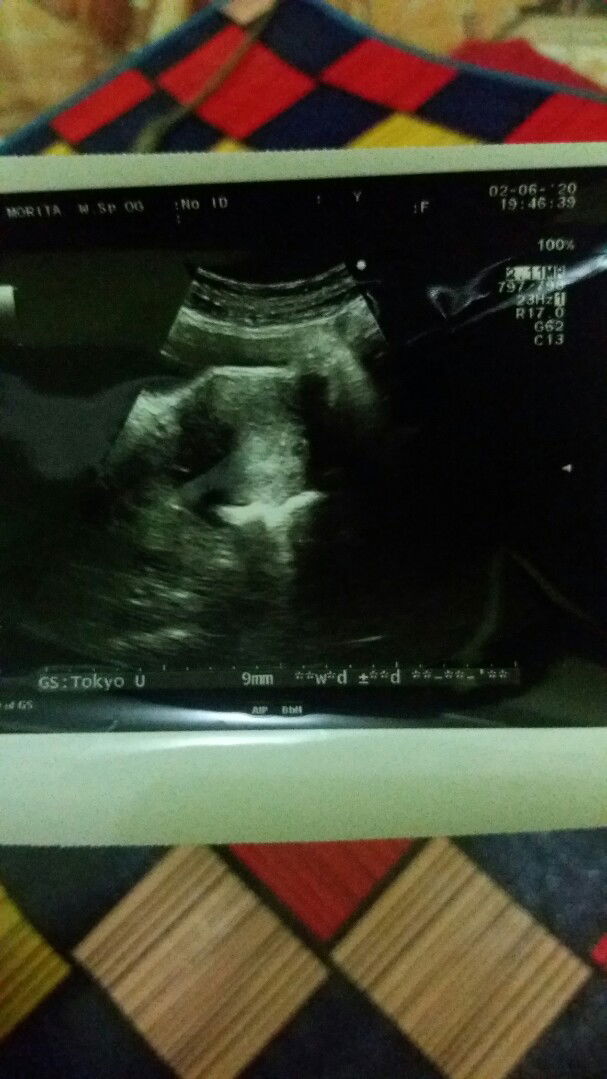

hasil USG

Bunda barusan saya abis dari dokter kehamilan saya 2 minggu .. saya awal haid 26 april sampe 3 mei. Adakah bunda2 disini mengerti hasil USG soalnya tadi lupa gak nanya ke dokternya

usg

Bunda bunda barusan saya abis dari dokter dan langsung USG perkiraan dokter usia kandungan baru 2 minggu.. saya haid pertama 26 april sampe 3 mei .. adakah yang tau maksud tulisan disebelah kanan itu apa? Soalnya tadi lupa gak nanyain.. makasih bunda